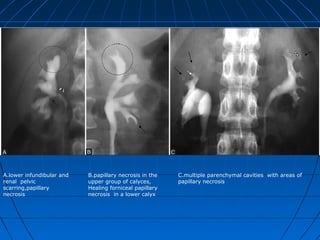

A.lower infundibular and

renal pelvic

scarring,papillary

necrosis

B.papillary necrosis in the

upper group of calyces,

Healing forniceal papillary

necrosis in a lower calyx

C.multiple parenchymal cavities with areas of

papillary necrosis

A.lower infundibular and renalpelvic scarring,papillary necrosis B.papillary necrosis in the upper group of calyces, Healing forniceal papillary necrosis in a lower calyx C.multiple parenchymal cavities with areas of papillary necrosis